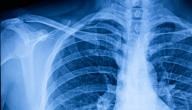

• طلب أشعة سينية لمنطقة الصدر.

• طلب الأشعة المقطعية للتحقق من وجود عدوى أو انسداد؛ مثل: ورم في الرئة أو انسداد في مجرى الهواء.